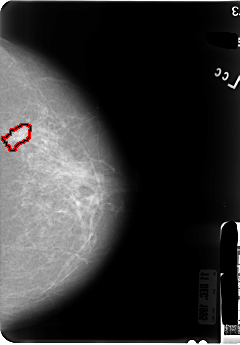

B_3046_1.LEFT_MLO

LEFT_MLO LINES 4760 PIXELS_PER_LINE 3424 BITS_PER_PIXEL 12 RESOLUTION 50 OVERLAY

FILE: B_3046_1.LEFT_MLO.OVERLAY

TOTAL_ABNORMALITIES 1

ABNORMALITY 1

LESION_TYPE MASS SHAPE IRREGULAR MARGINS SPICULATED

ASSESSMENT 4

SUBTLETY 3

PATHOLOGY MALIGNANT

TOTAL_OUTLINES 1

BOUNDARY